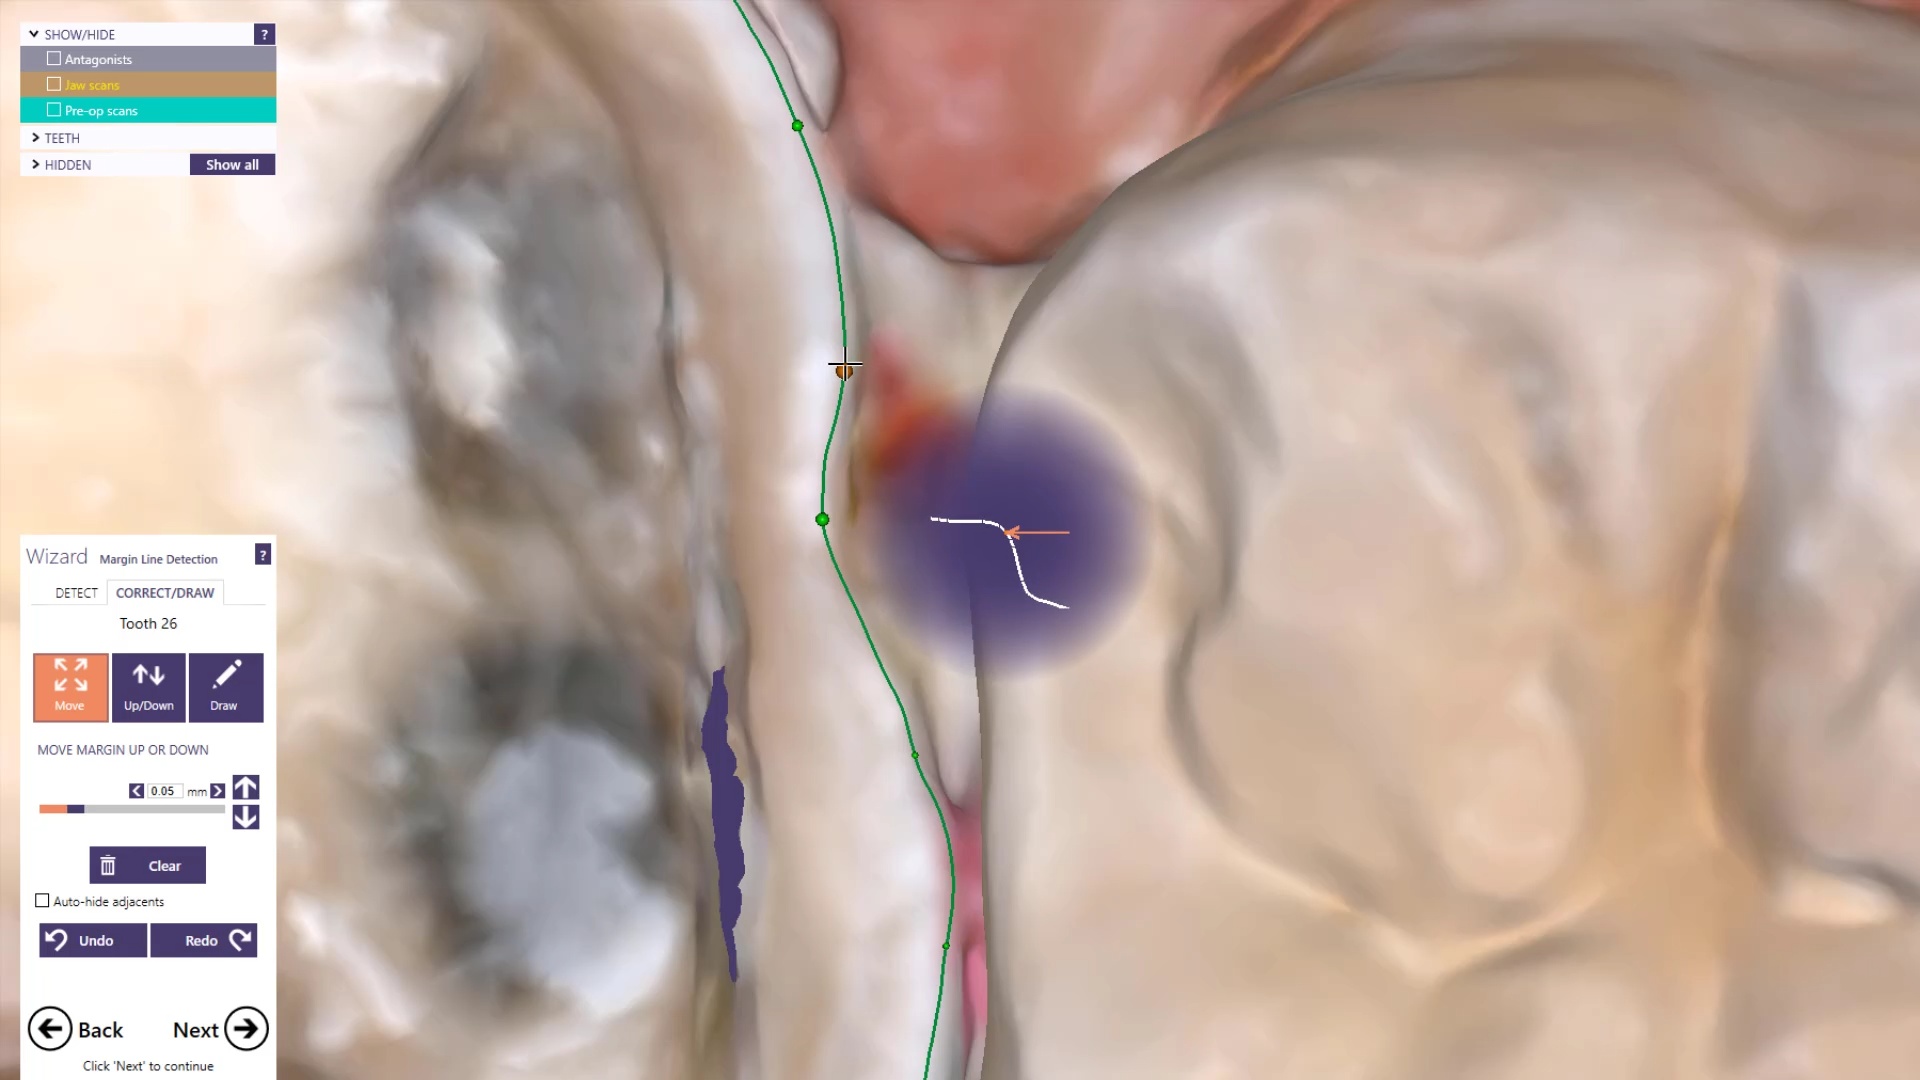

Once you have adequate clearance, retraction, and hemostatis, you can readily image and find your margins in the CAD software